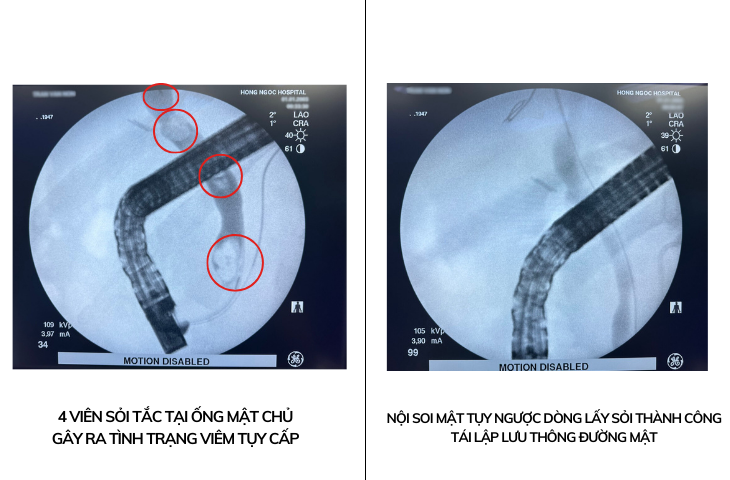

| Tình trạng ống mật chủ của bệnh nhân trước và sau khi được nội soi mật tụy ngược dòng lấy sỏi |

Kết quả, chỉ trong vòng 30 phút can thiệp, ekip đã thành công lấy 4 viên sỏi ở đường mật ra tá tràng, giúp bệnh nhân V.N tái lập lưu thông đường mật. Sau can thiệp, bệnh nhân hồi tỉnh tốt, có thể đi lại nhẹ nhàng, ăn uống bình thường trong vòng 2 giờ. Kiểm tra tình trạng viêm tụy cũng cải thiện rõ rệt, bệnh nhân có thể xuất viện 2 ngày sau đó.